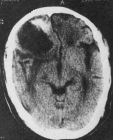

(1)頭痛。性質多較劇烈,常在清晨發作,有時在睡眠中被痛醒,但起床輕度活動後頭痛就會逐漸緩解或消失。(2)嘔吐。由於顱內壓力的增高,致使延髓呼吸中樞受到刺激,從而出現嘔吐,嘔吐多在頭痛之後出現,呈噴射狀。 (3)視力障礙。顱內壓增高時會使眼球靜脈血回流不暢,導致淤血水腫,損傷眼底視網膜上的視覺細胞,致視力下降。(4)精神異常。位於大腦前部額葉的腦瘤可破壞額葉的精神活動,引起興奮、躁動、憂鬱、壓抑、遺忘、虛構等精神異常表現。(5)單側肢體感覺異常或無力。位於腦半球中部的頂葉,專管感覺,該部位腫瘤常會導致單側肢體痛、溫、震動、形體辨別覺減退或消失。 (6)幻嗅。顳葉部腫瘤可在其刺激下出現幻嗅,即可聞到一種並不存在的氣味,如燒焦飯或焦橡膠等氣味。 (7)偏癱或踉蹌步態:小腦部病變更具特異性,即患者常在頭痛、嘔吐、視物障礙之後,出現偏癱或踉蹌的醉酒步態。 (8)耳鳴、耳聾。此種多在打電話時發覺,即一耳能聽到,另一耳則聽不到,該表現多是聽神經瘤的先兆。 肺癌腦轉移的表現多種多樣,故當出現上述徵象時應速去醫院進行詳細檢查,目前電子計算機斷層掃描(CT)和磁共振成像(MRI)對腦轉移瘤均能早期做出確切診斷,尤其推薦進行MRI檢查。治療

肝癌腦轉移根本的治療為全腦照射配合口服替莫唑胺治療,放射治療後由於被照射的腦組織發生水腫、病灶內組織壞死及血管改變可使顱內壓升高症狀加劇,應適當限制每日的攝水量,使用地塞米松或潑尼松龍和甘露醇等利尿劑,以減輕頭痛、嘔吐等症狀。伽馬刀治療是局部的放射治療,受到照射範圍的限制,對某些多發和單發病灶能緩解症狀,但對CT、MRI不能發現的微小轉移,不能有效地抑制,使放射後短期發生新的轉移,由於腦組織嬌嫩的特性限制了放射的劑量,一療程照射後很難再進行療程照射,因此對新發生的病灶治療較為困難。